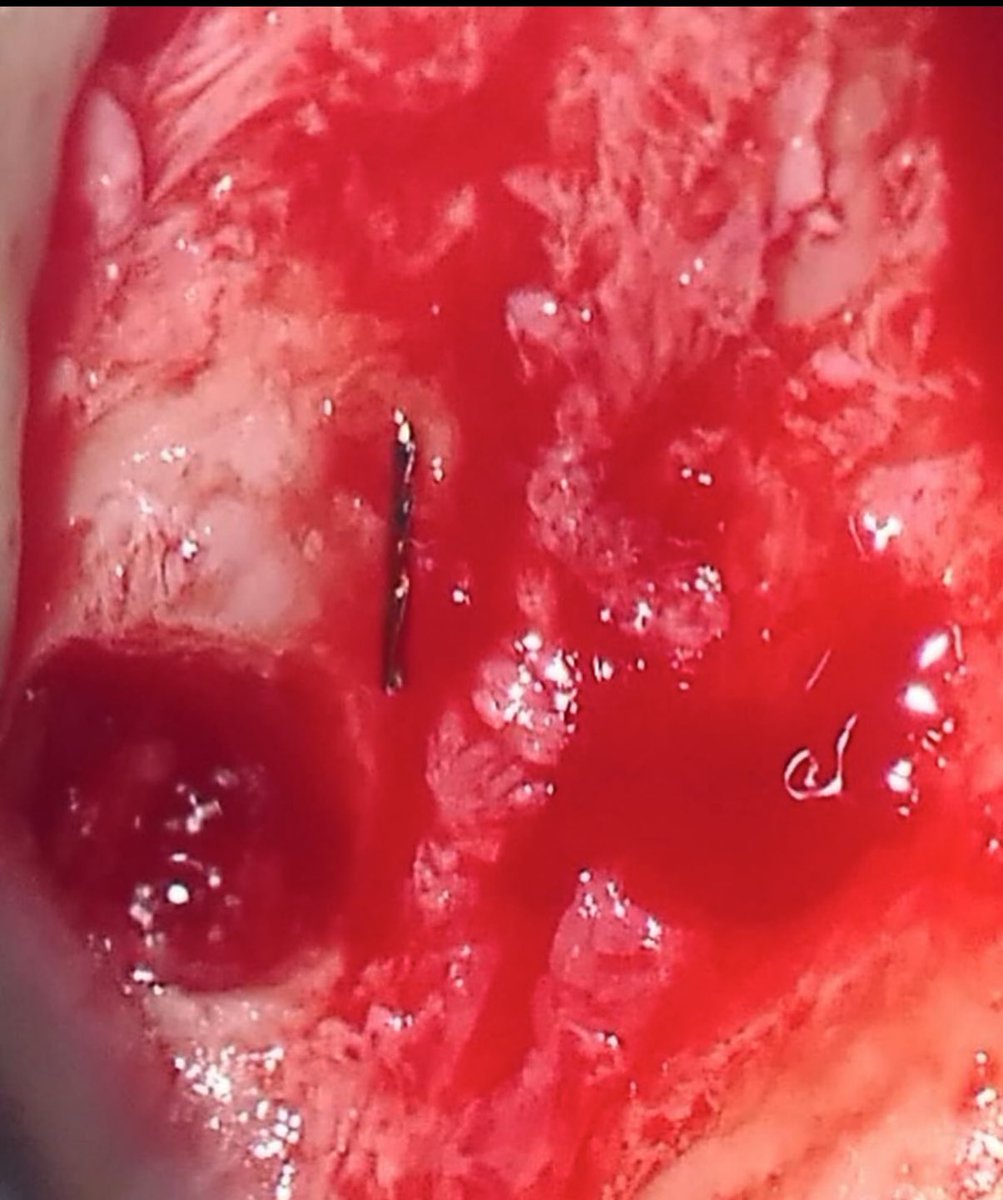

بسم الله نبدأ First endo surgery (Apicoectomy) for tooth #12 Dx: previously treated with symptomatic apical periodontitis + broken file beyond the apex

بسم الله نبدأ

First endo surgery (Apicoectomy) for tooth #12

Dx: previously treated with symptomatic apical periodontitis + broken file beyond the apex